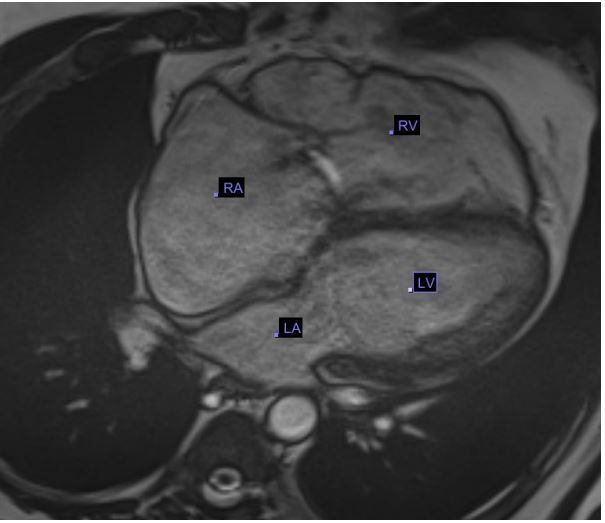

Over the following two days, vasoactive infusions were decreased and his lactate decreased went below 2 mmol/L. His repeat echocardiogram showed overall improvement with only minimal tricuspid regurgitation and follow up showed decrease in RA and RV size and normalization of function (Figure 4). He continued to require external cooling however, due to persistent fevers. He also had persistent severe hypoxic respiratory failure secondary to atelectasis that required FIO2 of 100% and inhaled nitric oxide.

Figure 4: Post OP TTE showing Prosthetic tricuspid valve, normalization of RA and RV size.